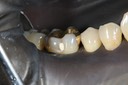

Wayne Chin #30 pre-op

Wayne Chin #30 prep

Wayne Chin #30 finish